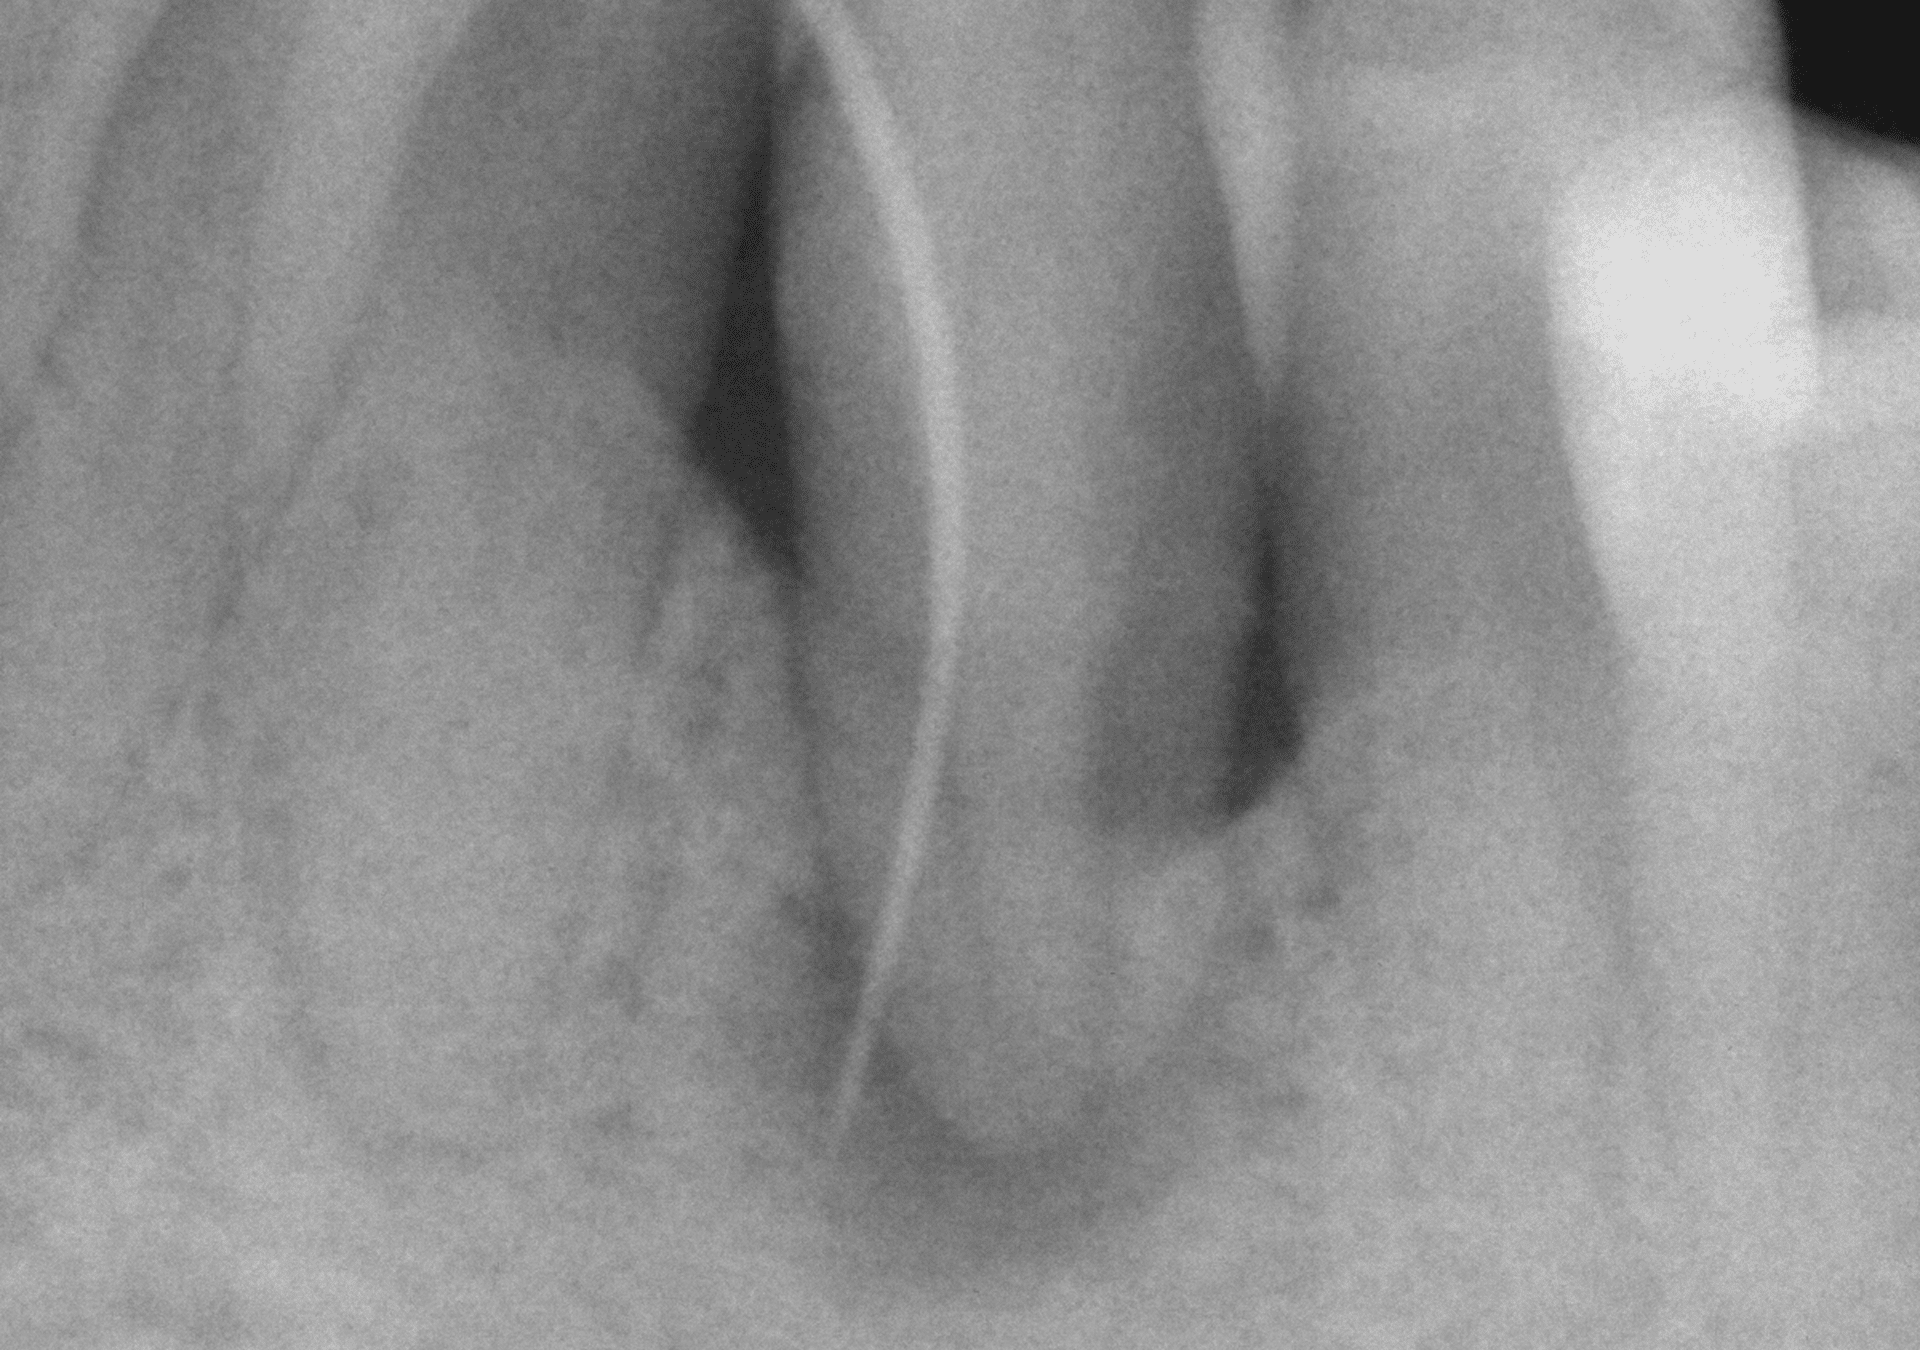

Endodoncia

- Amplia experiencia en tratamientos de endodoncia para resolver casos de alta dificultad.

- Diagnóstico y seguimiento con CBCT para analizar con exactitud los casos evaluados.